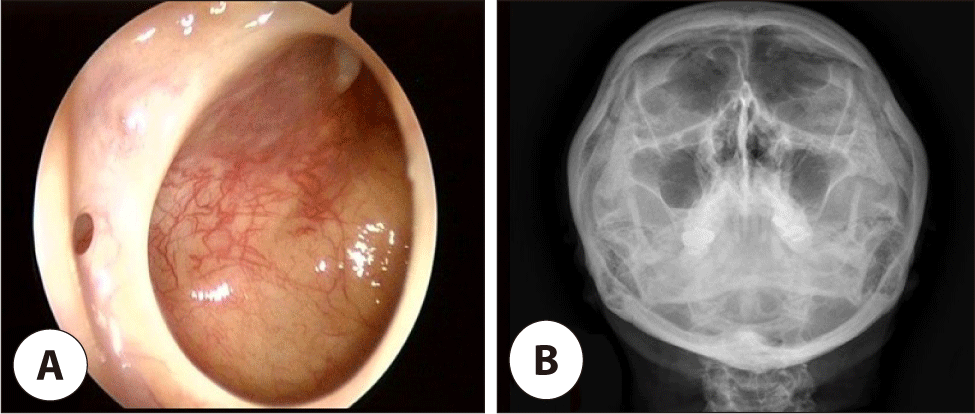

내원 당시 시행한 전비경과 비내시경 검사에서 좌측 중비도를 채우고 있는 비용종(nasal polyp) 소견과 후비루가 관찰되었고, 시행한 부비동 전산화 단층 촬영(computed tomography, CT)에서는 좌측 상악동 전체를 채우며 개구비도 단위(ostiomeatal unit)의 폐쇄를 보이는 연조직음영 소견과 함께 좌측 전두동과 사골동에도 부분적인 혼탁 소견을 보였다(Fig. 2).

jcohns-36-2-54-g2

Fig. 2. Preoperative computed tomography (CT) finding. A coronal view shows soft tissue densities at the left maxillary, ethmoid, and frontal sinuses.